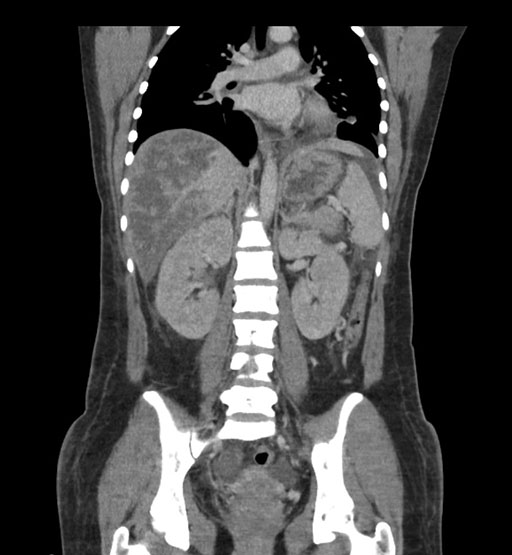

Coronal Arterial

Coronal Venous